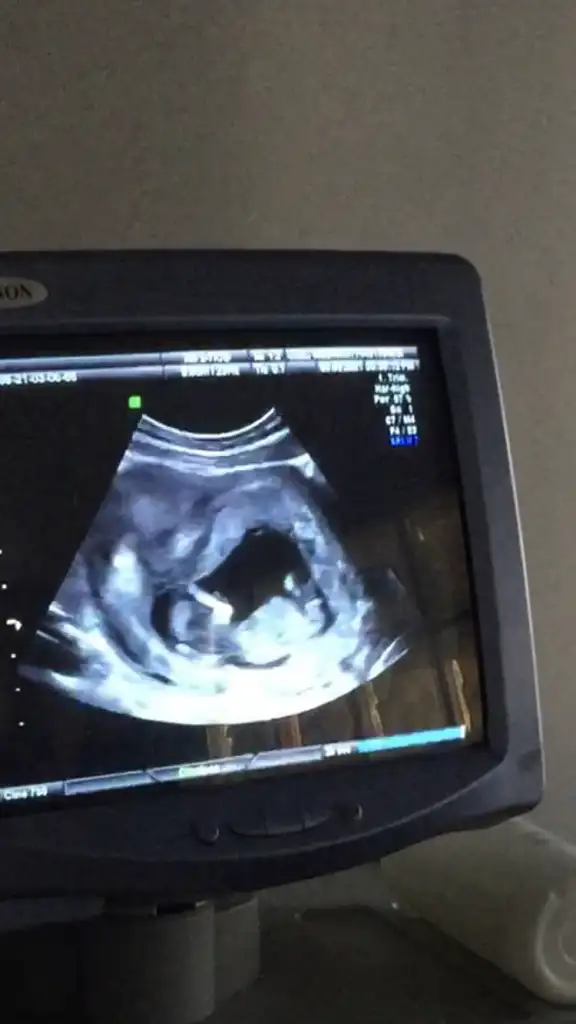

Ramzi teorisine göre ( bilimsel bir araştırma sonucuymuş ve %85 doğruluğu varmış). İlk 6-8 haftalık ultrason görüntüsüne göre bebeğin kesenin içersinde soldan ya da sağdan girişine göre cinsiyet tahmini yapılıyor. Bilimsel olunca tecrübeli annelerimiz yada anne adaylarımızdan yardım istiyoruz. Doğruluğu var mı öğrenmek adına :) Bizleri aydınlatırsanız çok seviniriz. bu teorieye göre;

Vajinal muayeneyle bakıldıysa eğer;

Sağdan girmiş gözüküyosa aslında solmuş ve ERKEK,

Soldan girmiş gözüküyosa aslında sağmış ve KIZ ,

Karından bakıldıysa eğer,

Soldan girmiş gözüküyosa gerçektede solmuş ve ERKEK,

Sağdan girmiş gözüküyosa gerçekte de sağmış ve KIZ,

Merhaba 7 hafta 5 günlük burada karından ultrasom abdominal cinsiyet tahmini alabilir miyim bende şimdiden teşekkür ederim.